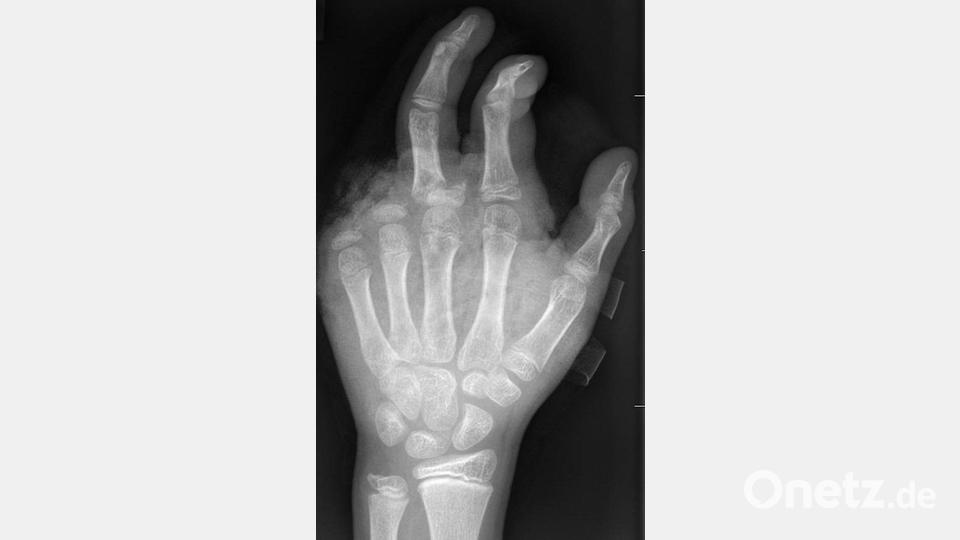

In der Handchirurgie müssten an Silvester im Unfallkrankenhaus rund 20 bis 40 Menschen mit Böllerverletzungen operiert werden, sagt die Ärztin. Dieses Jahr werde sie mir vier weiteren Handchirurgen im Einsatz sein. Die häufigsten Verletzungen entstünden durch explodierende Böller in der Hand.

„Der überwiegende Teil der Verletzungen trägt tatsächlich lebenslange Folgen mit sich, weil die Sprengkraft dazu führt, dass eben nicht nur einzelne Strukturen verletzt sind, sondern immer mehrere. Und das heilt praktisch nie ganz folgenlos ab.“ Zum Teil könnten Hände nicht mehr gerettet und müssten amputiert werden.